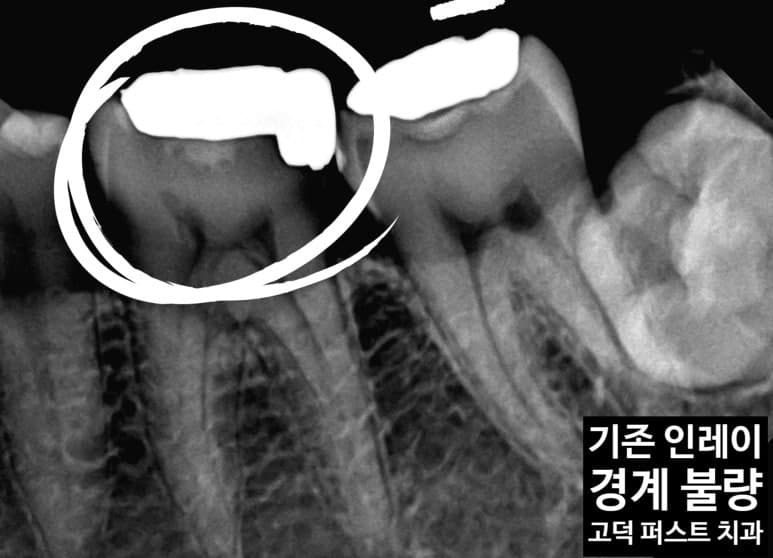

치료 전 상태 확인

기존 인레이 주변으로 경계 불량과 변색이 육안으로 확인됩니다. 하부에 2차 우식이 진행 중인 상태입니다.

엑스레이 진단

엑스레이상 인레이 변연부의 불량이 명확히 보입니다. 경계 틈새로 충치균이 침투해 2차 우식이 형성되어 있습니다.